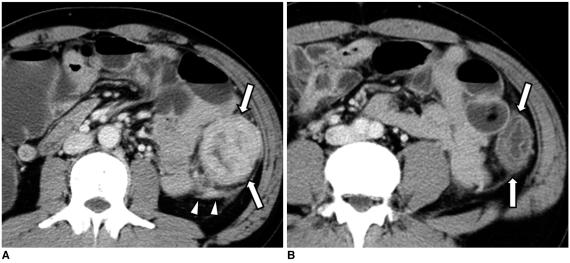

结肠癌相关结肠并发症的 CT 表现

CT findings of colonic complications associated with colon cancer.

A broad spectrum of colonic complications can occur in patients with colon cancer. Clinically, some of these complications can obscure the presence of underlying malignancies in the colon and these complications may require emergency surgical management. The complications of the colon that can be associated with colon cancer include obstruction, perforation, abscess formation, acute appendicitis, ischemic colitis and intussusception. Although the majority of these complications only rarely occur, familiarity with the various manifestations of colon cancer complications will facilitate making an accurate diagnosis and administering prompt management in these situations. The purpose of this pictorial essay is to review the CT appearance of the colonic complications associated with colon cancer.

结直肠癌患者可能会出现广泛的结肠并发症。临床上,这些并发症中的一些可能会掩盖结肠中潜在的恶性肿瘤,这些并发症可能需要紧急手术治疗。可能与结直肠癌相关的结肠并发症包括梗阻、穿孔、脓肿形成、急性阑尾炎、缺血性结肠炎和肠套叠。虽然这些并发症大多数很少见,但熟悉结直肠癌并发症的各种表现形式将有助于在这些情况下做出准确的诊断并进行及时的治疗。本文旨在通过 CT 影像回顾结直肠癌相关结肠并发症的表现。